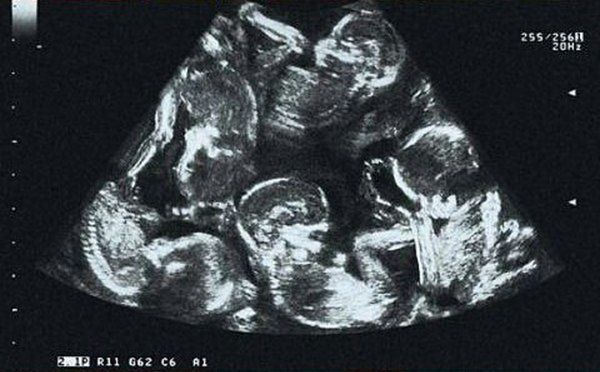

Niezwykłe zdjęcie z USG. Ile dzieci widzisz?

Kolejne badania sprawiły, że Alexandra była jednocześnie zachwycona i przerażona. Okazało się, że prawdopodobnie urodzi trojaczki. Jednak wraz z upływem tygodni, łatwiej było dostrzec płody. Wtedy też młodzi rodzice usłyszeli, że na świecie powitają nie dwoje, troje, nawet nie czworo dzieci, a pięcioraczki!

Niezwykłe zdjęcie z badania USG szybko trafiło do mediów społecznościowych, a Alexandra stała się pierwszą matką pięcioraczków w Czeskiej Republice.

Zdjęcie USG

Zdjęcie USG © Facebook